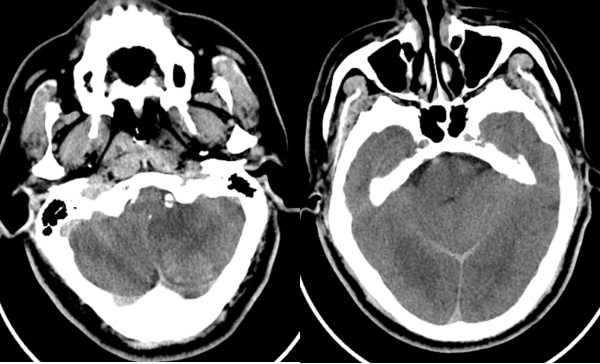

六十多岁的朱先生因“头晕19小时意识不清2小时”来到我院急诊,急诊神经科医师接诊后考虑脑血管疾病,立即行头颈部CTA+CTP检查,判断闭塞血管及梗死面积。影像科张卫国主任团体第一时间完成头颈CTA+CTP后处理,结果提示患者左侧椎动脉V1段起始处次全闭塞,右侧椎动脉V4段闭塞;基底动脉闭塞;双侧椎动脉供血区(双侧小脑、脑干、部分颞叶)缺血性灌注异常。

由于患者错过了4.5小时脑卒中静脉溶栓救治时间,无法溶栓治疗。郝永岗副主任带领神经血管介入团队评估病情后决定在全麻下为患者实施动脉取栓术,挽救处在缺血状态尚未坏死的脑组织。麻醉科李健主任第一时间到达导管室,保障手术顺利进行,术中可见患者基底动脉末端闭塞(基底动脉尖综合征)。医生运用SWIM技术取出黑红色血栓,复查造影显示:基底动脉远端血流通畅,双侧大脑后动脉、小脑上动脉显影。术中发现患者左侧椎动脉起始部重度狭窄,于病变处植入支架一枚,血管狭窄解除,术后送重症医学科继续治疗。

基底动脉尖综合征,是脑梗死的一种特殊类型,血管闭塞部位一般位于以基底动脉顶端为中心2cm范围内发出的2对动脉,即大脑后动脉和小脑上动脉与基底动脉末端交叉部位,可引起不同程度的意识障碍,死亡率高达50%。